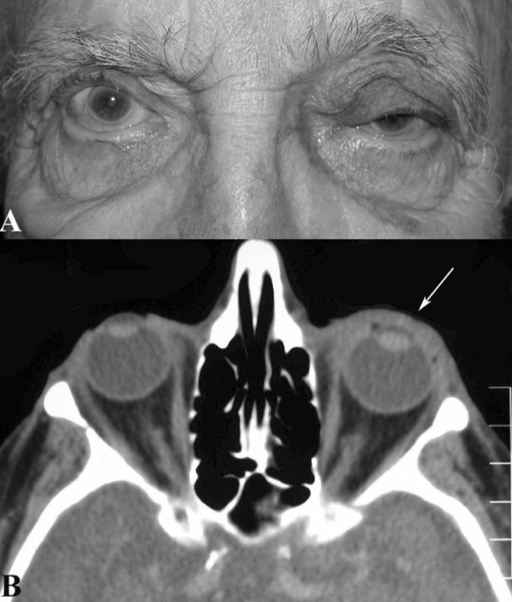

Figure 1: Orbital amyloidosis

Diffuse infiltration by amyloidosis seen throughout patient’s left anterior orbit (white arrow) without any posterior orbital involvement. (Reprinted from Periocular and Orbital Amyloidosis: Clinical Characteristics, Management, and Outcome. Ophthalmology 2006;113:1657-64 with permission from Elsevier.)[11]